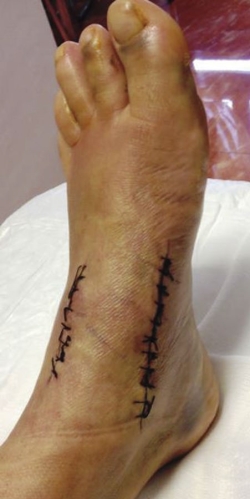

A pesar de un intento de tratamiento conservador con medicación y una ortesis, la sintomatología se fue incrementando, por lo que optamos por el tratamiento quirúrgico. Mediante un doble abordaje (Figura 5), dorsal y medial, se expuso el foco, se cruentaron los bordes, se redujo el hundimiento, se aplicó autoinjerto de cresta iliaca enriquecido con factores de crecimiento y se realizó una fijación con tornillos canulados.

Figura 5. Abordaje medial y dorsal.